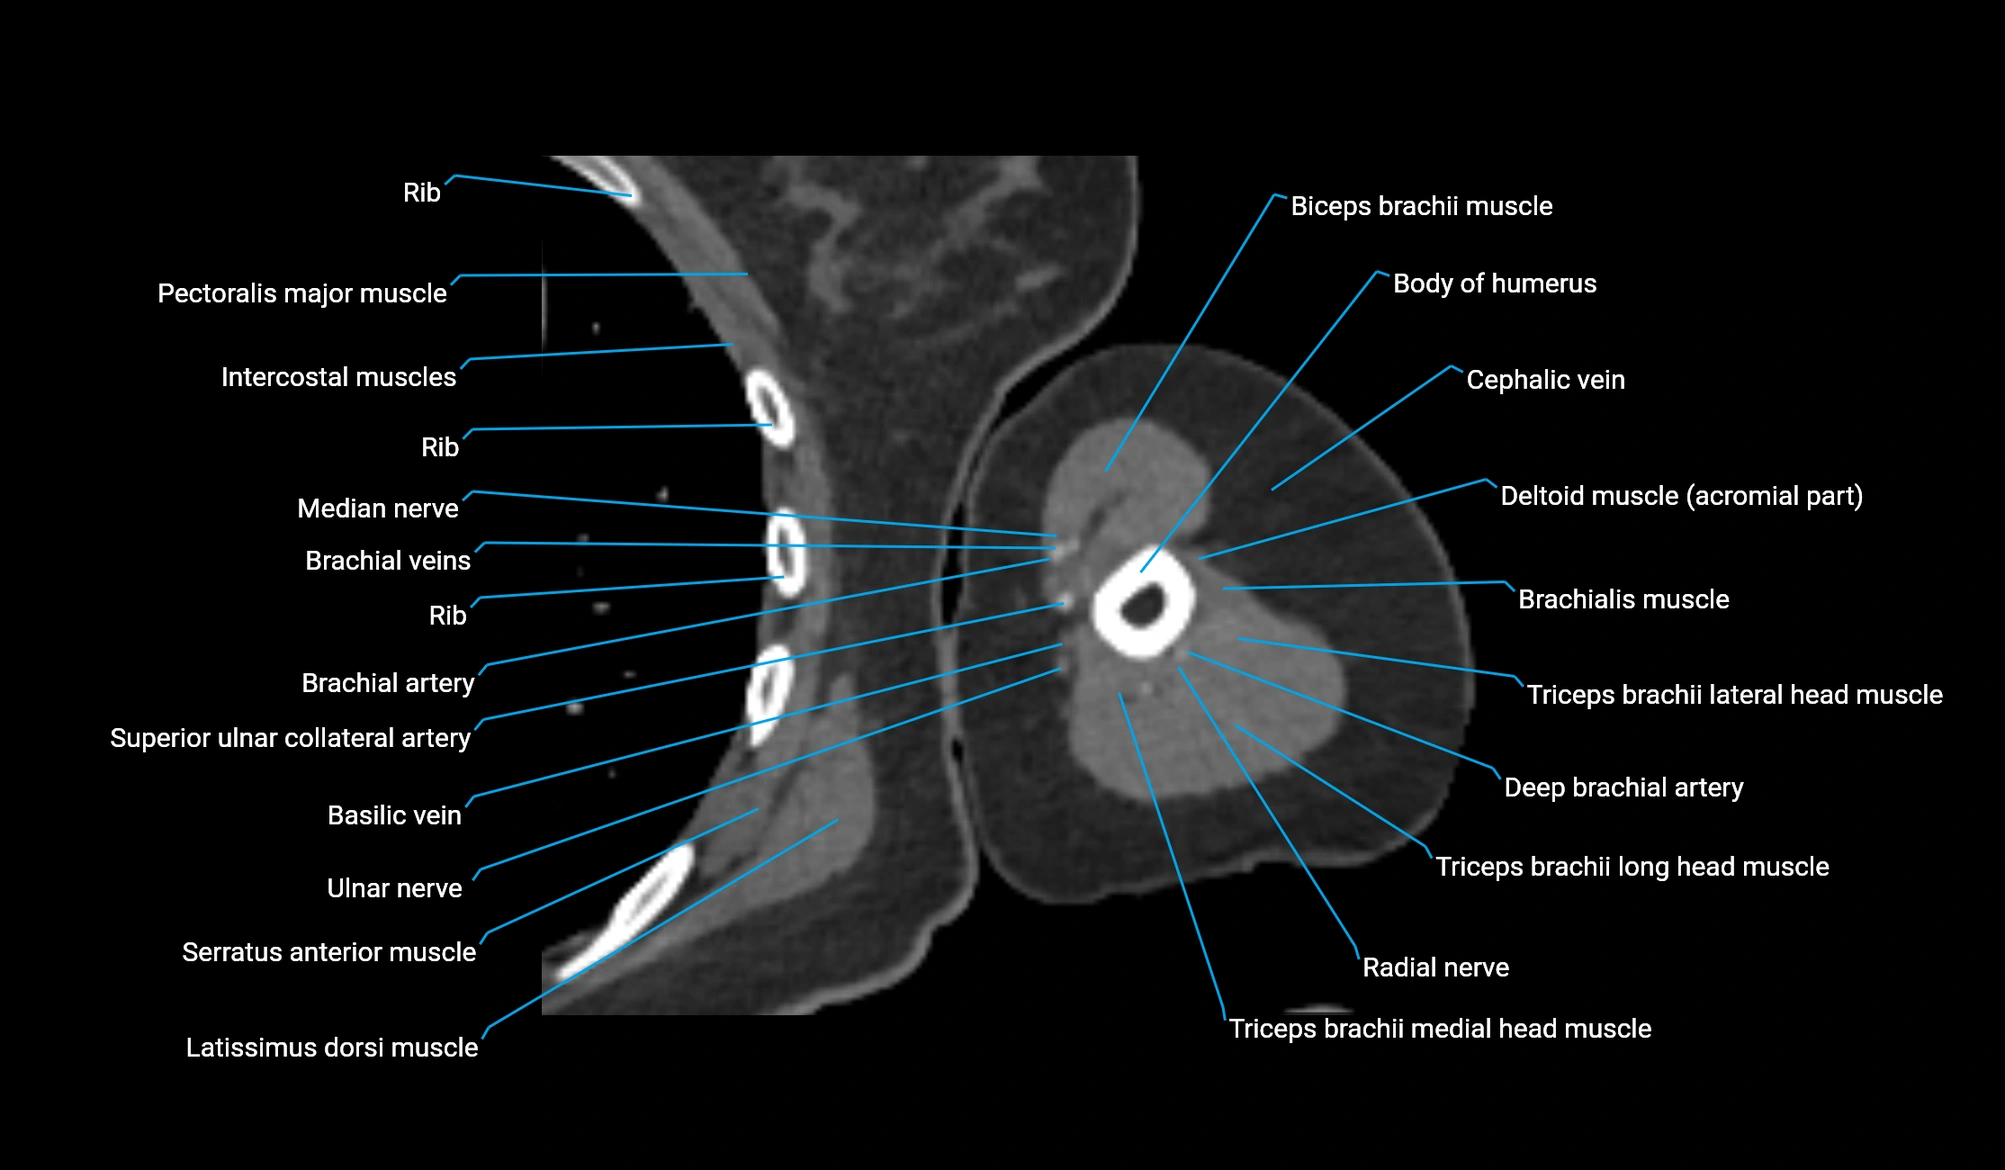

- Body of humerus

- Brachial artery

- Brachial fascia

- Brachialis muscle

- Cephalic vein

- Deep brachial artery

- Long head of triceps brachii muscle

- Lateral head of triceps brachii muscle

- Medial head of triceps brachii muscle

- Median nerve

- Radial nerve

- Superior ulnar collateral artery

- Ulnar nerve

- Basilic vein

- Biceps brachii muscle

- Pectoralis major muscle